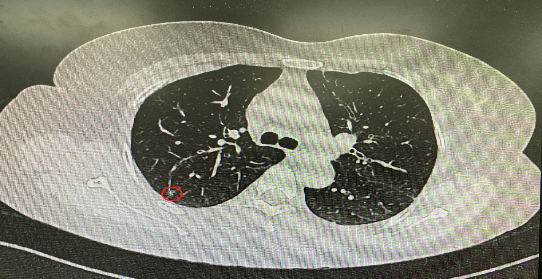

今年54歲的李女士(化名)7月初突然出現右上部腹痛,起初并未在意,以為稍作休息就會好轉,但疼痛卻并未消退,持續了一個星期。李女士實在難以忍受,才在家人陪伴下來到西安國際醫學中心醫院就診。胸外科二病區崔凱主任接診患者后,詳細詢問病情并查閱檢查資料,經胸部HRCT檢查,結果提示:右肺上葉后段混合密度結節影,考慮原位癌可能,即將患者收入胸腔外科二病區住院治療。

經與患者家屬溝通,崔凱主任決定行外科手術治療。為達到精準切除,術前需進行肺小結節切除前定位。由于結節位于右肺上葉后段,傳統經胸外穿刺術無法抵達病灶。崔凱主任與呼吸內科一病區歐陽海峰主任討論后,決定擬行LungPro全肺診療導航下染色定位。即術前通過Lung Pro導航規劃染色位置,經Lung Pro實時引導支氣管鏡抵達既定位置,注入亞甲藍染色劑標記結節位置。

使用術前規劃系統重建全肺3D模型,并于外科醫生討論染色位置,最終確定標記染色點—右肺上葉后段b亞段(RB2b)。術中使用P290(4.9mm外徑)標準支氣管鏡,根據導航術前規劃路徑,Lung Pro實時導航下,GS鞘管進入RB2b遠端官腔外病灶并注射亞甲藍染色劑。

一切準備就緒,7月15日,崔凱主任團隊聯合歐陽海峰主任團隊為患者行單孔胸腔鏡下右肺上葉后段切除術,手術用時128分鐘順利完成。進入胸腔后,亞甲藍染色部位明顯,患者發生癌變的右肺上葉后段被成功切除。術后標本根據染色部位迅速找到結節,剖開位置兼染色位置和病灶完全符合,行術中冰凍后快速送病理檢查。經術后病理檢查,明確診斷為(右肺上葉)原位腺癌。